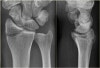

X-ray : 원위 요골 골절(Volar-type Barton's fracture)

X-ray : 원위 요골 골절(Dorsal-type Barton's fracture)